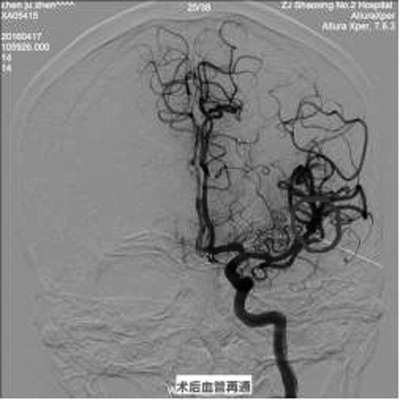

4月17日,我院成功为一位发病1小时到院的急性大血管脑梗死患者联合应用静脉溶栓、动脉内支架取栓、动脉溶栓等多种方法,在发病后3小时19分时开通血管。

该患者4月17日早晨7:30于骑车时突发右侧肢体完全不能活动,跌倒在地,伴言语表达、理解不能,意识模糊。经急诊静脉溶栓、动脉内支架取栓、动脉溶栓、后续康复治疗后,患者已能独立行走,语言理解正常,能部分语言表达。